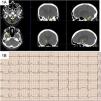

Caso clínico 1Varón de 77 años ingresado por diverticulitis sigmoidea perforada. Portador de vía venosa central yugular derecha que se retiró estando el paciente sentado. Inmediatamente después, presentó hipotensión arterial y disminución del nivel de consciencia con apertura ocular espontánea, mirada fija sin obedecer órdenes y localizando dolor con hemiparesia izquierda. TC craneal con burbujas de aire en senos cavernosos y cisternas de la base sin presentar otras alteraciones (fig. 1A). El electrocardiograma (ECG) mostró elevación del segmento ST en derivaciones precordiales y onda T negativa en V5, V6, I y aVL (fig. 1B) con elevación de marcadores de daño miocárdico. Ingresó en UCI presentando a las pocas horas una crisis tónico-clónica generalizada descartándose etiología tóxica, metabólica e infecciosa. Se realizó ecocardiograma transtorácico que no mostró comunicación interauricular. Se inició tratamiento general con fluidoterapia, oxigenoterapia por mascarilla a alto flujo y anticomiciales, presentando una evolución favorable. A las 24 horas, el ECG se normalizó, descendieron las enzimas miocárdicas y en TC craneal de control se comprobó la reabsorción de las burbujas de aire. El paciente fue dado de alta de UCI a las 72 horas con exploración neurológica normal. Diagnóstico: embolismo aéreo venoso retrógrado tras retirada de vía venosa central.